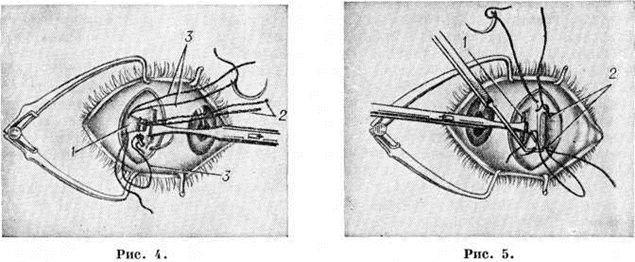

К операциям первого типа относятся: резекция — укорочение мышцы посредством иссечения её участка у места прикрепления к склере и подшивание к этому же месту (рисунок 4); тенорафия — укорочение мышцы путём образования складки из её сухожилия; прорафия — перемещение сухожилия мышцы кпереди (при вмешательствах на прямых мышцах) или кзади (при вмешательствах на косых мышцах) с образованием складки или без неё.

Ослабляют действие мышцы следующие операции: свободная (или полная) тенотомия — пересечение сухожилия мышцы у места прикрепления без подшивания её к склере; тенотомия с ограничительным (предохранительным) швом — фиксация тенотомированной мышцы на некотором расстоянии от места анатомического прикрепления при помощи шва, проходящего через это место и край пересечённого сухожилия; частичная тенотомия — нанесение на сухожилие мышцы с противоположных краёв двух-трёх неполных, несколько отстоящих друг от друга разрезов; рецессия (рисунок 5) — перемещение мышцы, отсечённой у места прикрепления, кзади (при вмешательствах на прямых мышцах) или кпереди (при вмешательствах на косых мышцах) с подшиванием её к склере; пролонгация — удлинение мышцы путём полной перерезки её сухожилия в разных направлениях и сшивания перерезанных участков. Операцию свободной тенотомии производят только на косых мышцах.